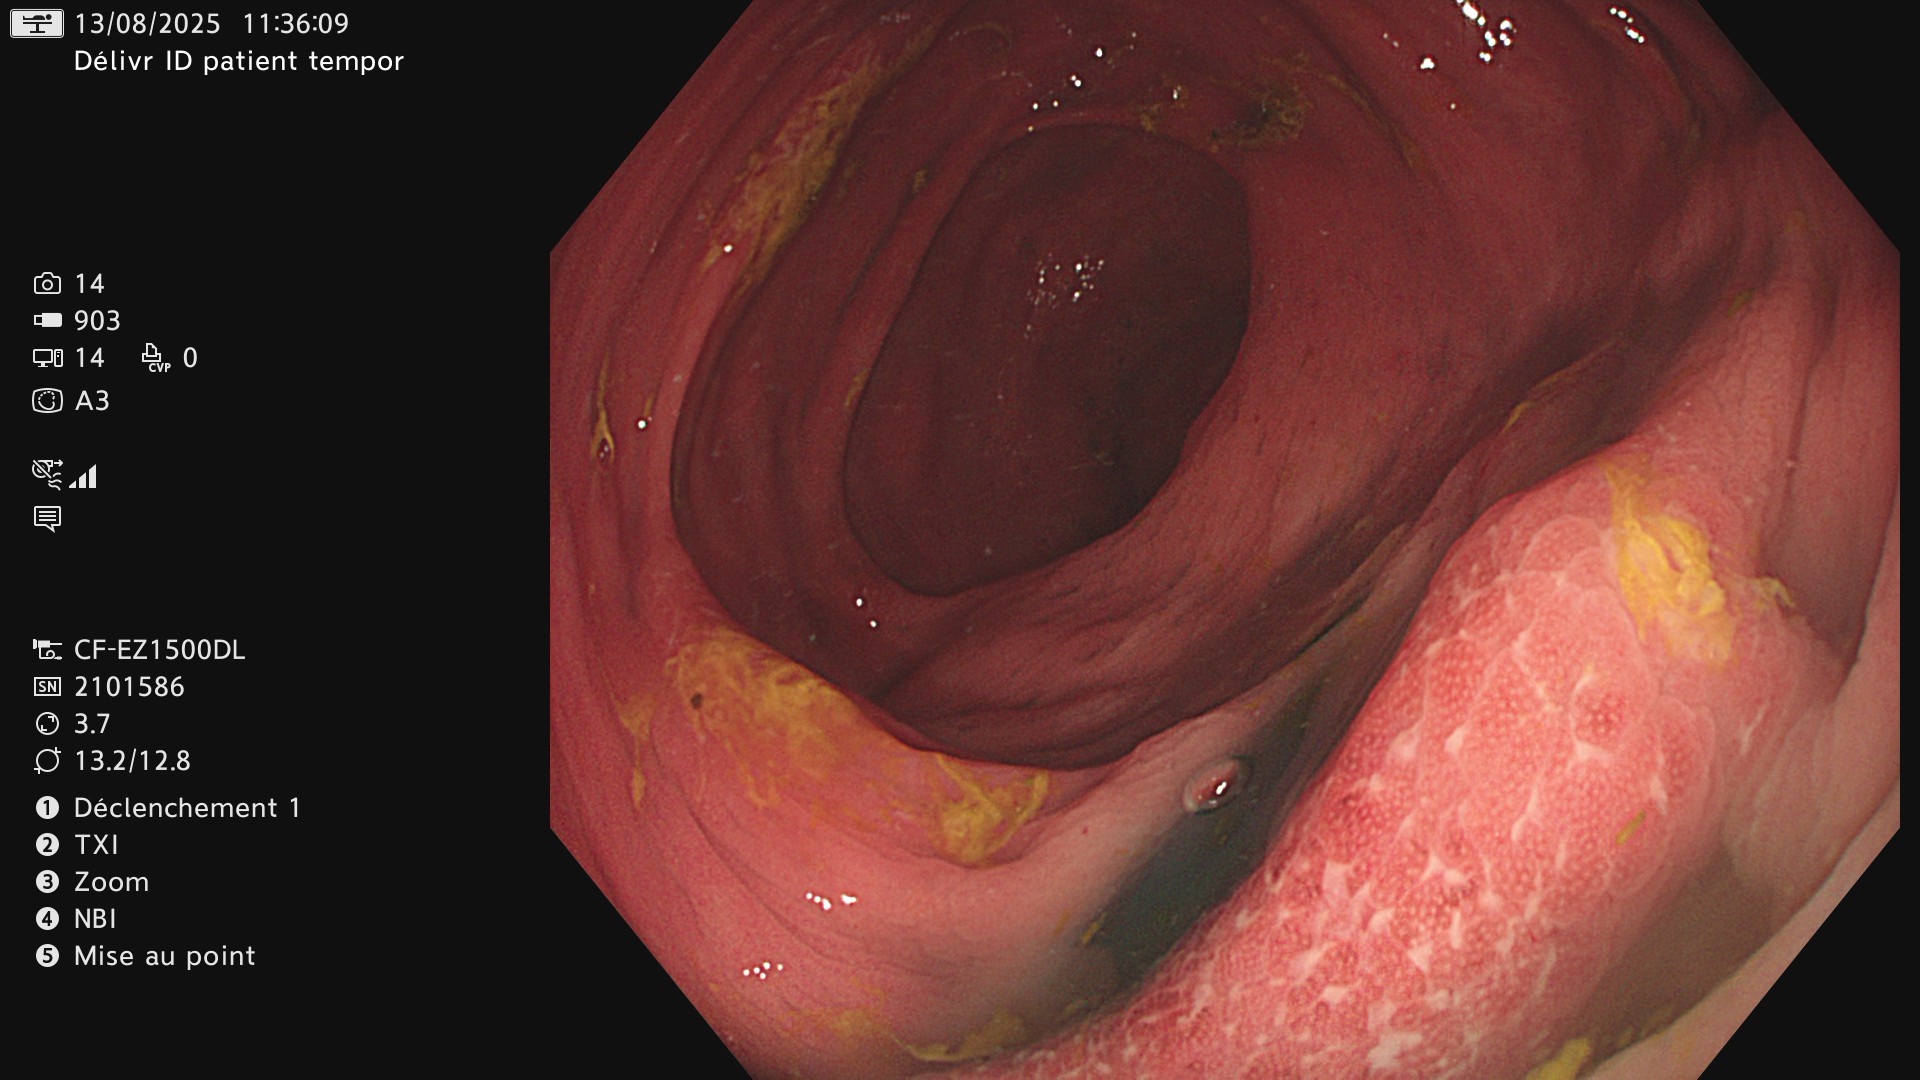

Maladie presque cicatrisée

Ci-dessous, en endoscopie on constate aussi que la maladie garde des petites plages actives sur un colon qui semble presque cicatriciel.

Même aspect en chromoendoscopie virtuelle NBI